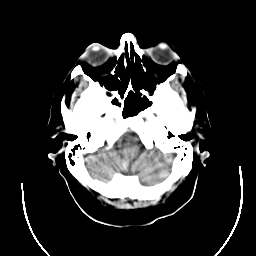

CT Study #3 -- Slice #5